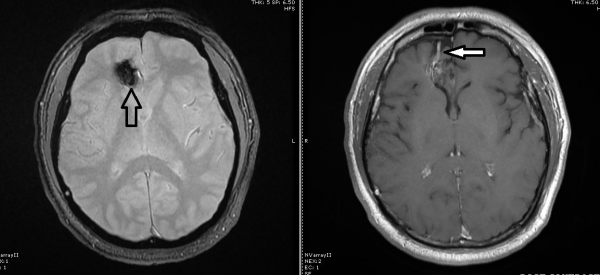

见到汤米时,我第一件事就是问他有没有癫痫、头痛和呕吐,他斩钉截铁地说没有。我仔细研究造影图,只见肿瘤直径约 2×2.5×3公分,肿瘤呈实质固态状而非弥漫状,周遭有旧患出血留下的血迹。

3个月后,我和汤米又见面了,新的脑造影图显示肿瘤并没有任何变化,确诊是海绵状血管瘤,在这个阶段,不需要医治。